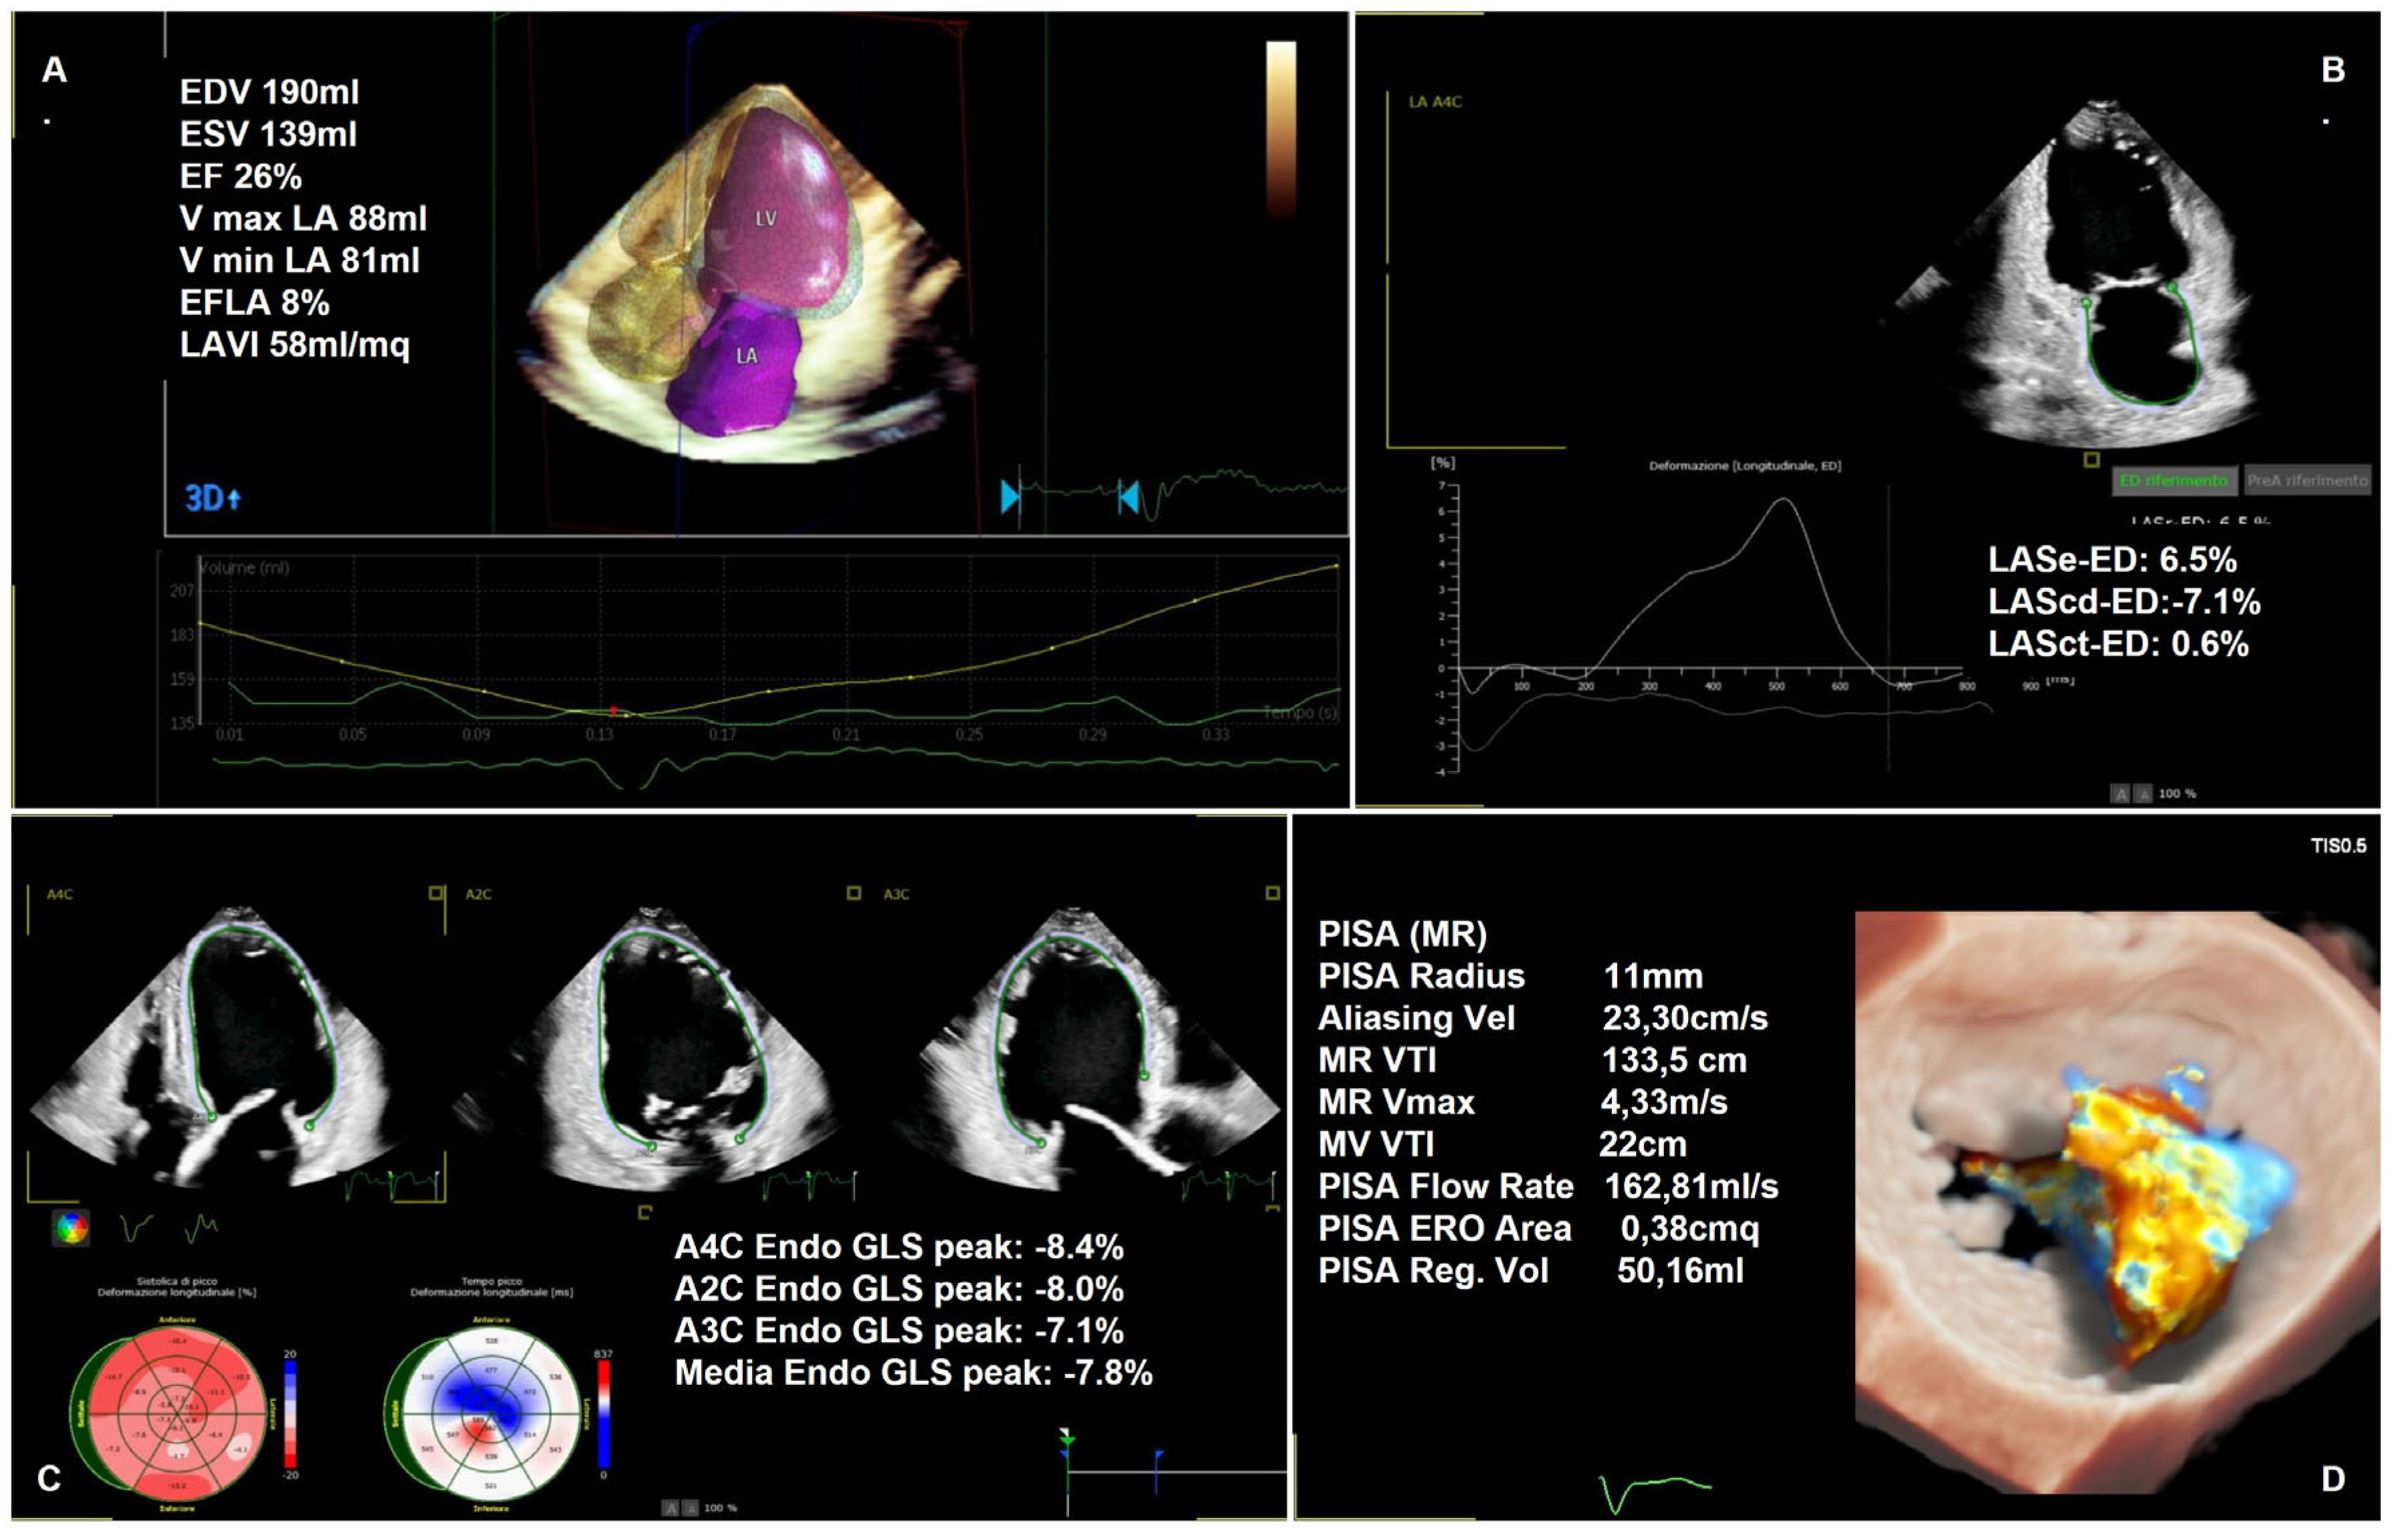

1.2.2. Semi-Quantitative and Quantitative Assessment

1.4. Heart Remodeling Evaluation